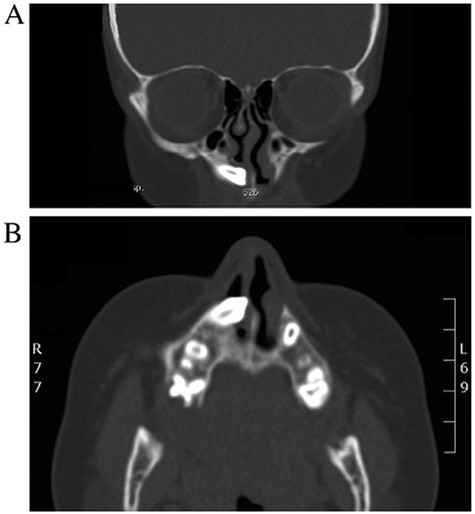

A 13-years-old boy medically and surgically free presented to the otolaryngology clinic with swelling of the right side of the face for 1 month, no other significant symptoms. Patient has history of facial trauma 8 years back. Examination was unremarkable apart from right-sided facial swelling over the maxillary sinus. Computed tomography (CT) of the paranasal sinuses showed a large expansible cystic lesion in the right maxillary bone that arises from the maxillary alveolar ridge with superior extension and displacement of the right maxillary sinus. A displaced tooth is seen within the anterior aspect with its root pointing posteriorly to the floor of the hypoplastic maxillary sinus with its crown embedded within the lesion (Fig. 1).

CT scan of maxillofacial bones showing a large expansible cystic lesion in the right maxillary bone that arises from the maxillary alveolar ridge with superior extension and displacement of the right maxillary sinus as well as remodeling of the floor of the right orbit with slight narrowing of the right inferior orbital fissure.